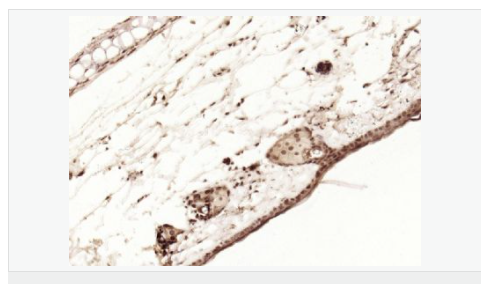

| 产品应用 | WB=1:1000-2000 ELISA=1:1000-5000 IHC-P=1:100-500 IHC-F=1:100-500 Flow-Cyt=1ug/Test ICC=1:100-500 IF=1:100-500 (石蜡切片需做抗原修复) not yet tested in other applications. optimal dilutions/concentrations should be determined by the end user. |